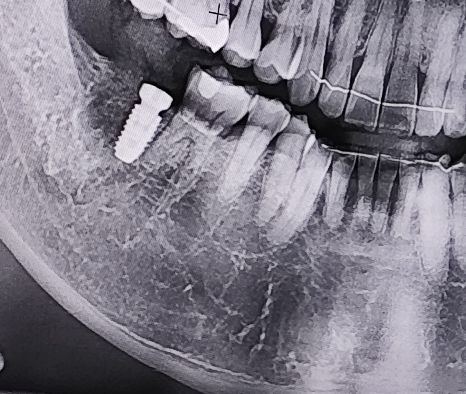

생애 첫 임플란트를 시작했다. 작년에 크라운을 씌웠던 오른쪽 어금니를 염증 때문에 발치했고 뼈가 차오르기를 기다려 오늘 나사를 박았다. 뼈가 차기는 했는데 부족해서 뼈 이식이란 것도 병행했다. 사진에 보면 뼈가 덜 차오른 것처럼 보인다. 이식한 뼈와 나사와 완전히 결합되기 까지 4개월 정도 걸린다고 한다. 오래 걸리는 일이다. 잠시 대기하는 동안 치과 의자에 앉아서 이전 환자의 차트를 얼핏 봤는데 사진에 보이는 나사만 다섯개다.